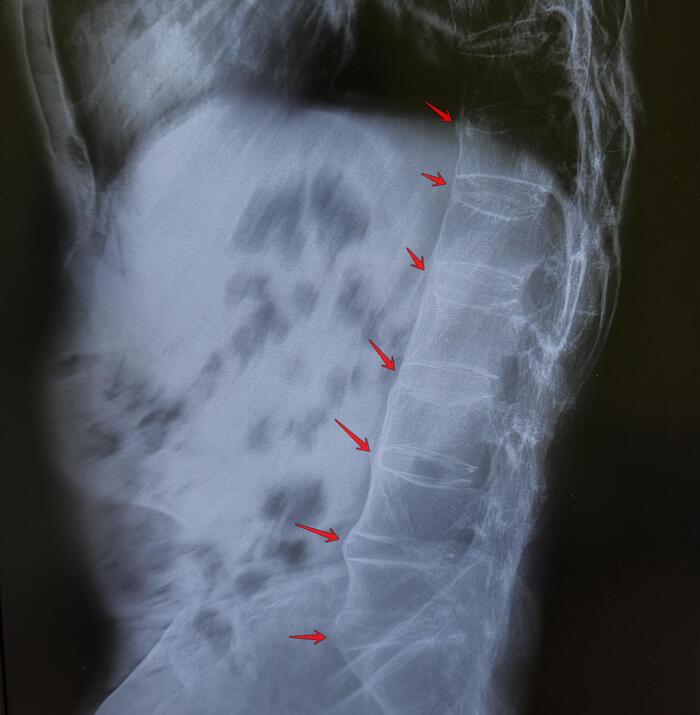

Рентгенография - в начальной стадии при подагре почти не дает информации; при длительном течении, когда кристаллы накапливаются внутри кости, их видно как четкие округлые образования - “пробойник ”.

При пирофосфатной артропатии иногда можно увидеть кальцификацию суставного хряща.

- Рентгенография - в основном для исключение перелома (если была травма), определения стадии деструкции сустава.